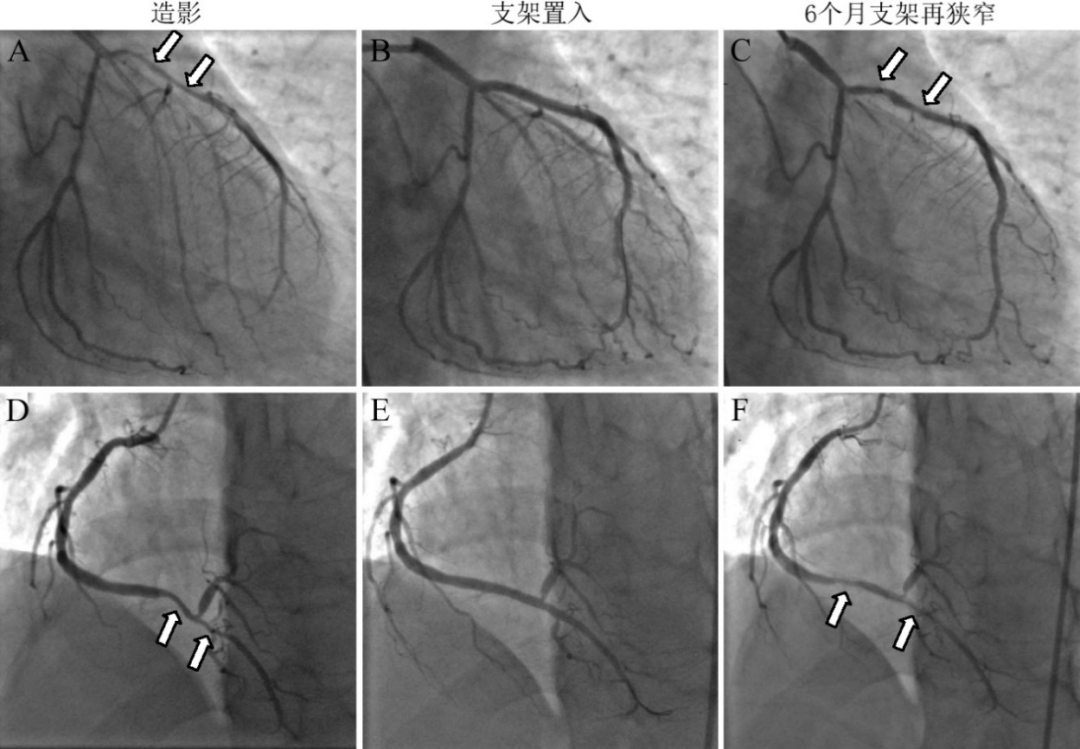

冠状动脉痉挛患者支架内再狭窄发生率远远高于其余支架置入患者,临床疗效低于临床预期[12, 13]。我们早期研究发现7例患者在药物洗脱支架置入后3例发生支架内再狭窄,再狭窄率达到42.9%,另有2例支架内膜轻度增生(图9)[1]。

图9 冠脉痉挛支架置入后再狭窄。临床确诊为变异性心绞痛,前降支近中段狭窄90%(A),右冠远段狭窄75%(D)。冠脉内多次给予硝酸甘油200ug,狭窄未消失。前降支近中段置入Taxus药物洗脱支架2枚,右冠远段1枚,即刻效果良好(B,E)。术后规则服用波立维、阿司匹林、他汀和地尔硫卓等药物,6个月后复查造影,前降支支架内再狭窄70%,累及高位对角支次全闭塞(C),右冠支架内再狭窄60%(F)。白色箭头指示狭窄或支架内再狭窄部位。